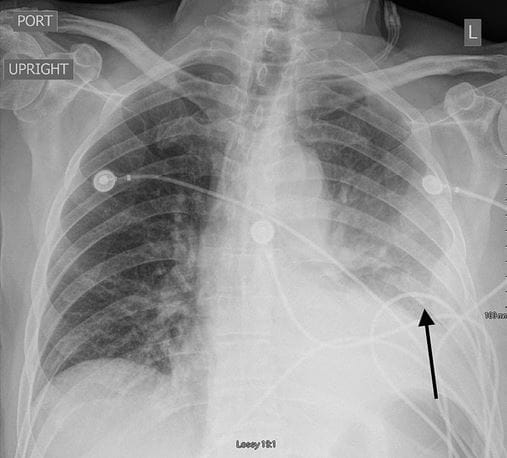

Outre les cas d’inflammations cardiaques (myocardites) qui sont les plus mis en avant, de plus en plus d’études commencent à soulever d’autres effets toxiques des vaccins. Récemment, des cas d’épanchement pleural unilatéral ont été signalés. L’épanchement pleural se caractérise par une accumulation anormale de liquide dans l’espace pleural (la région entre les deux couches de la membrane mince qui recouvre les poumons).